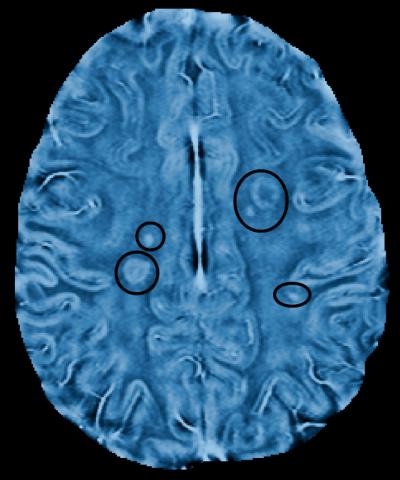

Researchers at the University of British Columbia have developed a new magnetic resonance imaging (MRI) technique that detects the telltale signs of multiple sclerosis in finer detail than ever before – providing a more powerful tool for evaluating new treatments.

The technique analyzes the frequency of electro-magnetic waves collected by an MRI scanner, instead of the size of those waves. Although analyzing the number of waves per second had long been considered a more sensitive way of detecting changes in tissue structure, the math needed to create usable images had proved daunting.

Once scars in the myelin, known as lesions, appeared in conventional MRI scans, Rauscher and his colleagues went back to earlier frequency-based images of those patients. Looking in the precise areas of those lesions, they found frequency changes – indicating tissue damage – at least two months before any sign of damage appeared on conventional scans. The results were published according to research published in the June 12, 2013, issue of Neurology ®, the medical journal of the American Academy of Neurology.